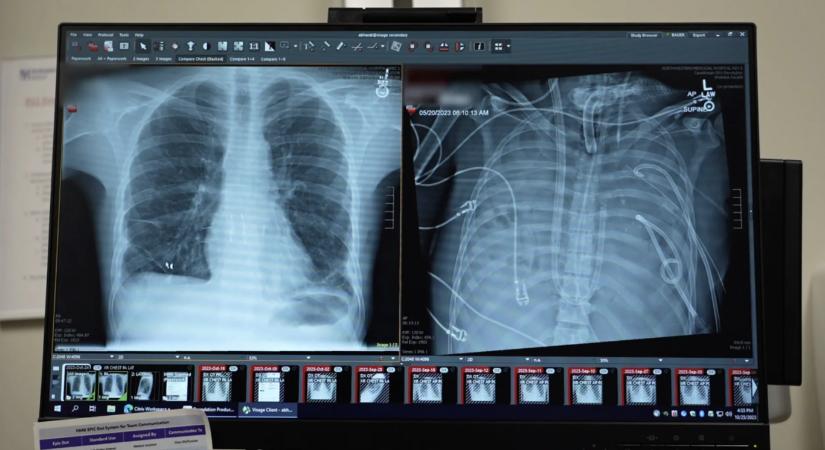

A 33 éves férfi több szerve leállt egy influenzából kiinduló fertőzés után, ezért orvosai eltávolították mindkét tüdejét, és egy mesterséges rendszerrel tartották életben.